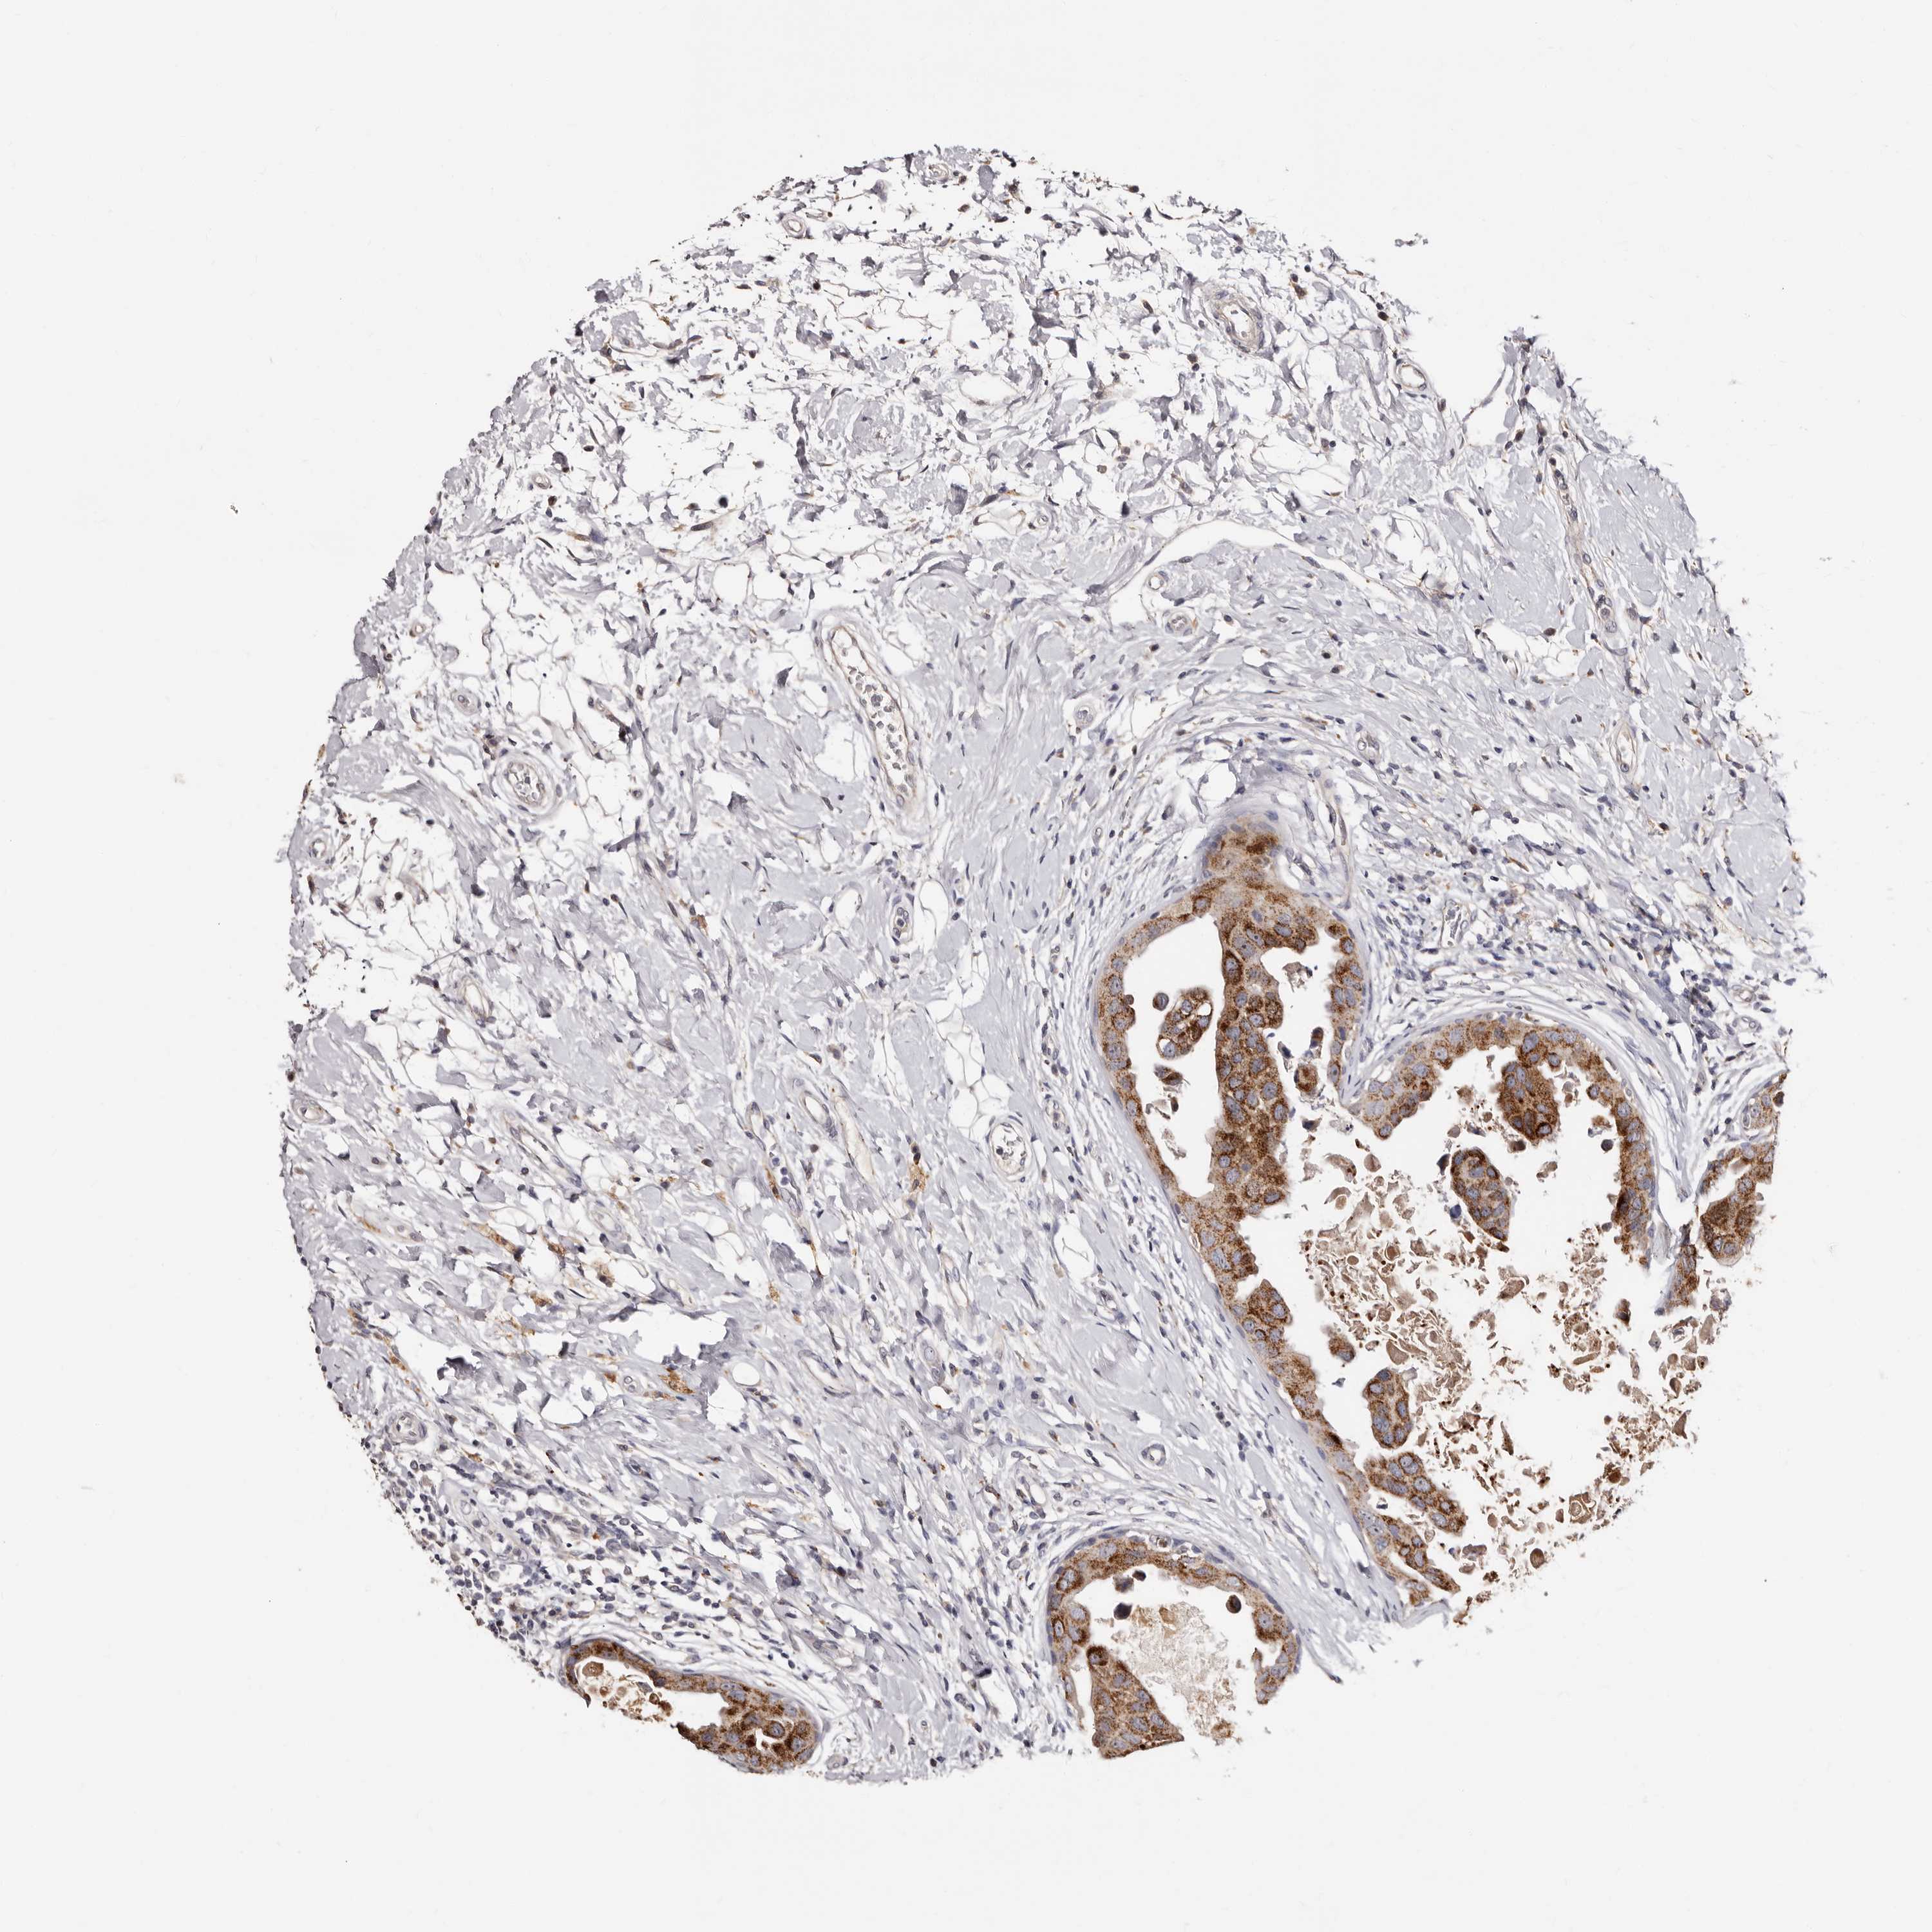

CANCER BREAST CANCER Show tissue menu

BRCA TCGA BRCA VALIDATION PROTEIN EXPRESSION